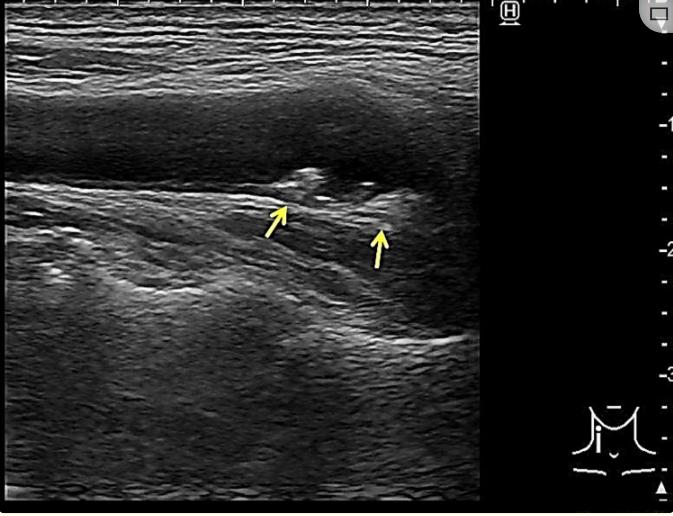

除了轻微升高的C-反应蛋白(0.32 mg/dL)、血糖(118 mg/dL)和γ-谷氨酰转肽酶(75 U/L)外,血液检查并无异常。神经传导研究显示结果正常。扩散加权和T2加权液体衰减反转恢复脑部MRI显示左侧中央前回PK高信号(图1)。脑部磁共振血管造影否认主动脉闭塞。经食管超声心动图显示无血栓、右向左分流或主动脉弓病变。颈动脉超声心动图显示两个眼球上都有斑块,内膜中层厚度(IMT)增厚,但血流速度没有增加(图2)。

图1、脑部核磁共振成像的结果

(A,B)弥散加权脑轴MRI显示左侧中央前回中央前结节(PK)高信号(箭头)。(C,D)弥散加权脑冠状MRI显示左侧中央前回高信号(箭头)。(E,F)T2加权液体衰减反转恢复脑冠状MRI显示左侧中央前回高信号,与扩散加权成像(箭头)一致